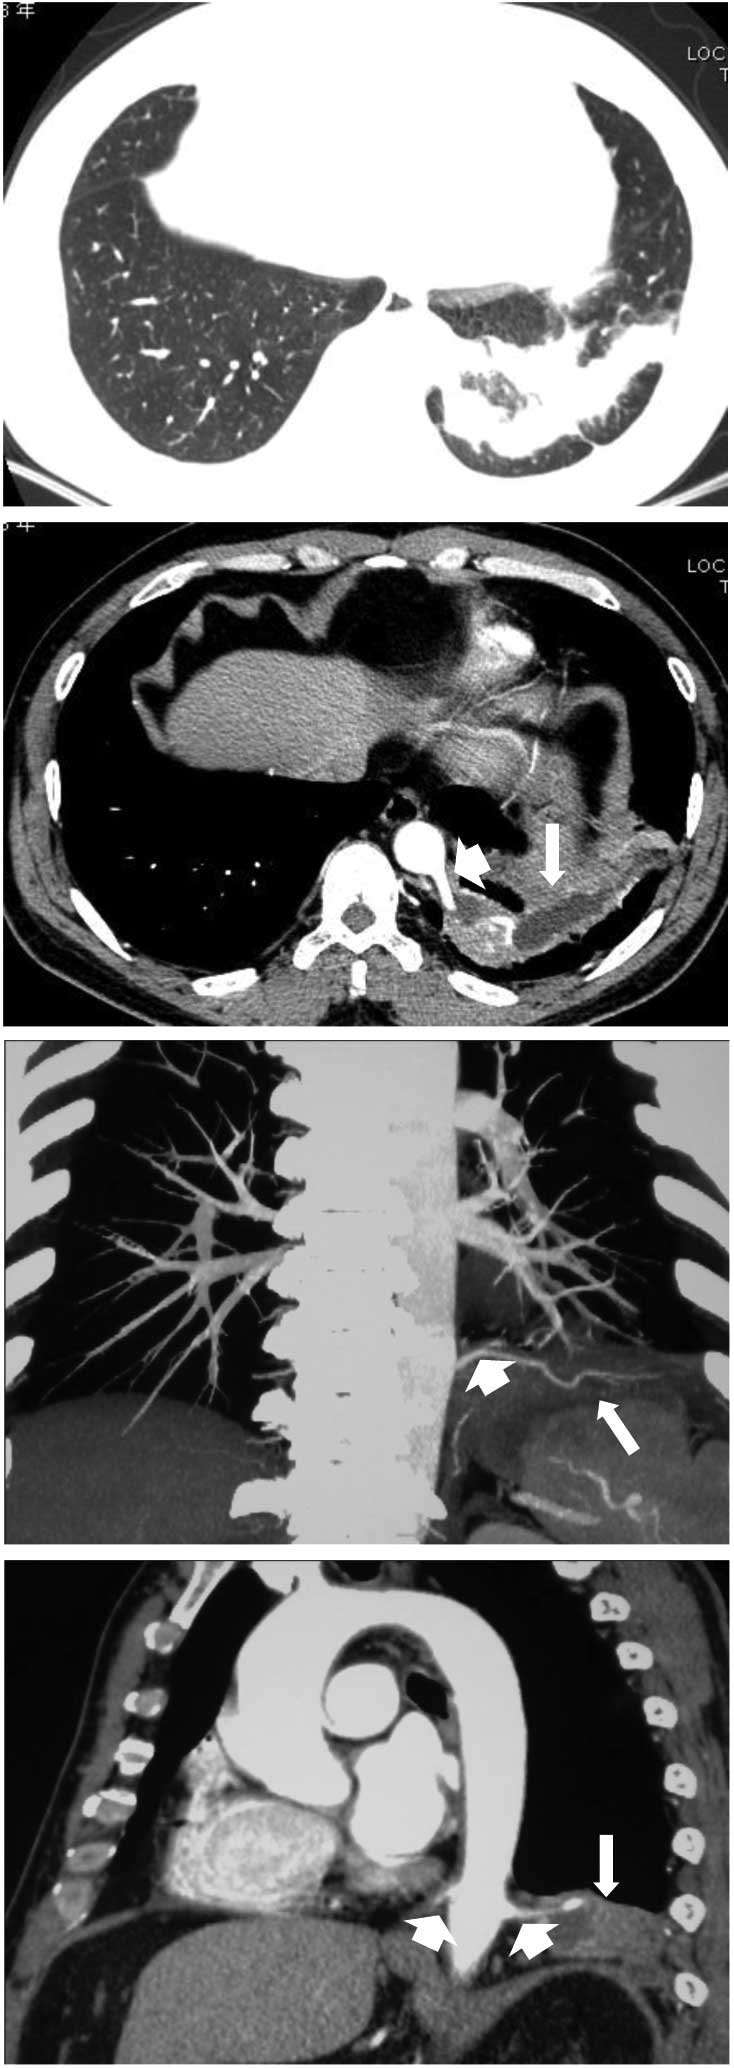

The patient was a non-smoker and had no family history of pulmonary tuberculosis (TB) or bronchiectasis. However, the patient had pneumonia in 2009, which was cured following antibiotic treatment. The physical examination showed no abnormalities and the laboratory examination revealed a marginal increase in serum γ-guanosine triphosphate (80 IU/l) and serum CA19-9 levels increased to 1,242.85 U/ml. To exclude the possibility of an underlying abnormal malignant lesion, esophagogastroduodenoscopy, endoscopic ultrasonography, colonoscopy, abdominal ultrasonography and computed tomography (CT) were performed with no specific abnormalities identified. A chest X-ray that was performed on admission of the patient to hospital showed a dense shadow cord strip in the left lower region (Fig. 1). In addition, chest high-resolution CT scanning and 3D image reconstruction further indicated anomalous arteries arising from the descending thoracic aorta (Fig. 2). Pulmonary sequestration was diagnosed, and surgery confirmed the presence of two aberrant arteries arising from the thoracic aorta and entering the left lower lobe basal segment. The sequestrated lung was consolidated and tightly connected to the diaphragm (Fig. 3). A left lower lobectomy was performed and the postoperative pathological observations were consistent with intralobar pulmonary sequestration. Immunohistochemistry staining using a monoclonal antibody against human CA19-9 (Maixin Biotechnology, Fuzhou, China) demonstrated marked positive staining for CA19-9 in the ciliated cylindrical epithelia, alveoli and particularly in the mucus of the cysts (Fig. 4). Following pulmonary resection, the symptom of bloating improved and the serum CA19-9 levels rapidly decreased to within the normal range (34.5 U/ml; Fig. 5).

Figure 2

Chest high-resolution computed tomography scanning and 3D image reconstruction showed a mass in the left lower lobe and two anomalous arteries (short arrow) arising from the descending thoracic aorta and extending into the sequestered lung (long arrow).